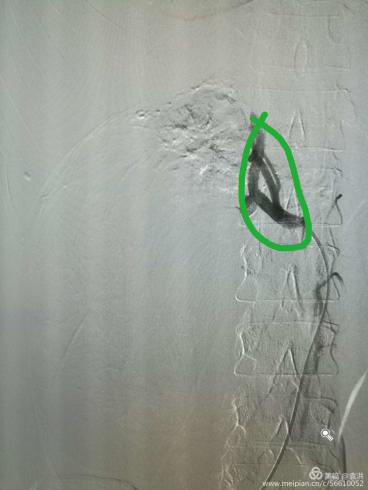

(介入栓塞后,腫瘤血液供應(yīng)完全阻斷

大大降低了手術(shù)出血風(fēng)險(xiǎn))